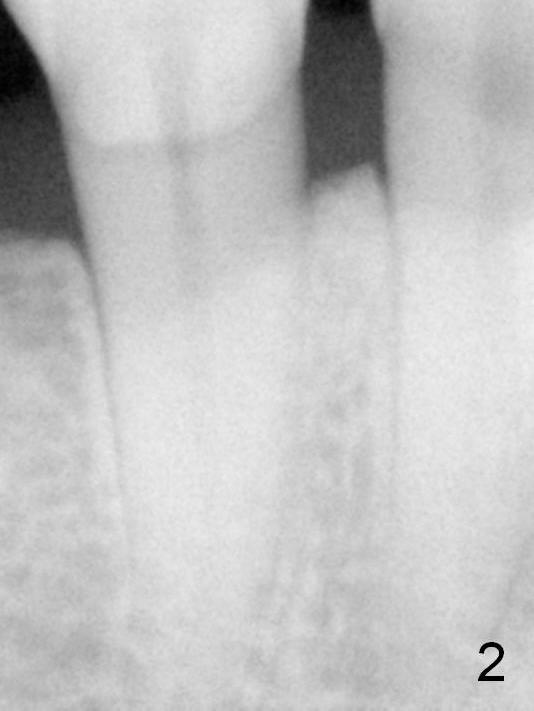

Fig.2: Pre-orthodontic PA of the tooth #29.